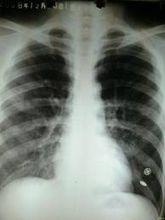

症狀:左下葉實變,呈灰白色,肺葉明顯腫脹

大葉性肺炎X線檢查,可見大葉性或段性分布的均勻性密度增高陰影。病變消散時,滲出物溶解液化,肺部可聞及捻發音,X線表現為散在不均勻片狀陰影,約在2~3周后陰影方完全消散。抗生素治療,可縮短病程,減輕病變,合併症也大為減少。